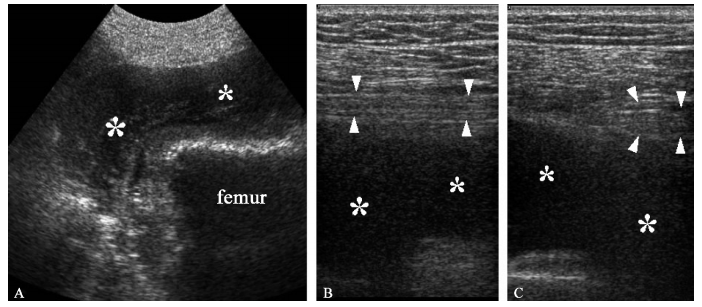

A. 髋关节后方12~4MHz超声矢状继面显示断髋关节置换术后发生的一个部分性大血肿(* )。坐骨神经12~5MHz超声矢状断面(B)和短轴断面(C)显示在积血(* )部位坐骨神经移位和受牵拉(箭头端)然而,检查者应该意识到超声对于探查这么深区域的轻微病变敏感性较低,尤其是肥胖患者;对于显示近端的梨状肌处的病变和坐骨大孔处的病变亦不敏感。尤其梨状肌综合征时由于坐骨神经在坐骨大切迹处被压引起下背部及坐骨神经痛,超声亦不能显示,因为神经走行于臀肌深面,位置很深。同样的,对于梨状肌肥大及其他异常超声也难以提供可靠的信息。因此,MRI在准确诊断梨状肌综合征及与其他可能造成下腰部疼痛的原因进行鉴别的方面优于超声。